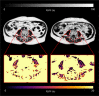

Cachexia, a multifactorial wasting syndrome, is highly prevalent among advanced-stage cancer patients. Unlike weight loss in healthy humans, the progressive loss of body weight in cancer cachexia primarily implicates lean body mass, caused by an aberrant metabolism and systemic inflammation. This may lead to disease aggravation, poorer quality of life, and increased mortality. Timely detection is, therefore, crucial, as is the careful monitoring of cancer progression, in an effort to improve management, facilitate individual treatment and minimize disease complications. A detailed analysis of body composition and tissue changes using imaging modalities-that is, computed tomography, magnetic resonance imaging, (18F) fluoro-2-deoxy-D-glucose (18FDG) PET and dual-energy X-ray absorptiometry-shows great premise for charting the course of cachexia. Quantitative and qualitative changes to adipose tissue, organs, and muscle compartments, particularly of the trunk and extremities, could present important biomarkers for phenotyping cachexia and determining its onset in patients. In this review, we present and compare the imaging techniques that have been used in the setting of cancer cachexia. Their individual limitations, drawbacks in the face of clinical routine care, and relevance in oncology are also discussed.